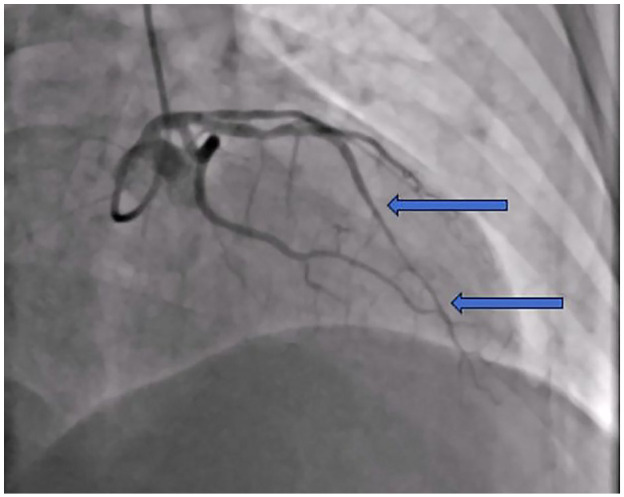

In this paper, we present 2 patients with ST-elevation myocardial infarction in the course of Spontaneous Coronary Artery Dissection. The first patient, a female admitted with STEMI, was diagnosed with SCAD with intravascular imaging and treated with IVUS-guided PCI. In the second patient, a young male hospitalized due to angina and STEMI, SCAD was not identified initially, and the patient was treated conservatively. Based on these cases, we show different faces of the same disease that imply different diagnostics and management strategies. We draw attention to the fact that the disease affects not only young women without atherosclerotic risk factors and that it is not always possible to avoid generally not recommended invasive treatment and anticoagulant therapy. The paper also discusses the disease's pathophysiology and its diagnosis methods.

本文报告2例自发性冠状动脉剥离过程中st段抬高型心肌梗死。第一位患者是一名入院的STEMI女性患者,通过血管内成像诊断为SCAD,并接受ivus引导的PCI治疗。第二例患者为年轻男性,因心绞痛和STEMI住院,最初未发现SCAD,患者接受保守治疗。基于这些病例,我们展示了同一疾病的不同面貌,意味着不同的诊断和管理策略。我们提请注意的事实是,这种疾病不仅影响没有动脉粥样硬化危险因素的年轻女性,而且通常不推荐的侵入性治疗和抗凝治疗并不总是可以避免的。本文还讨论了该病的病理生理及诊断方法。